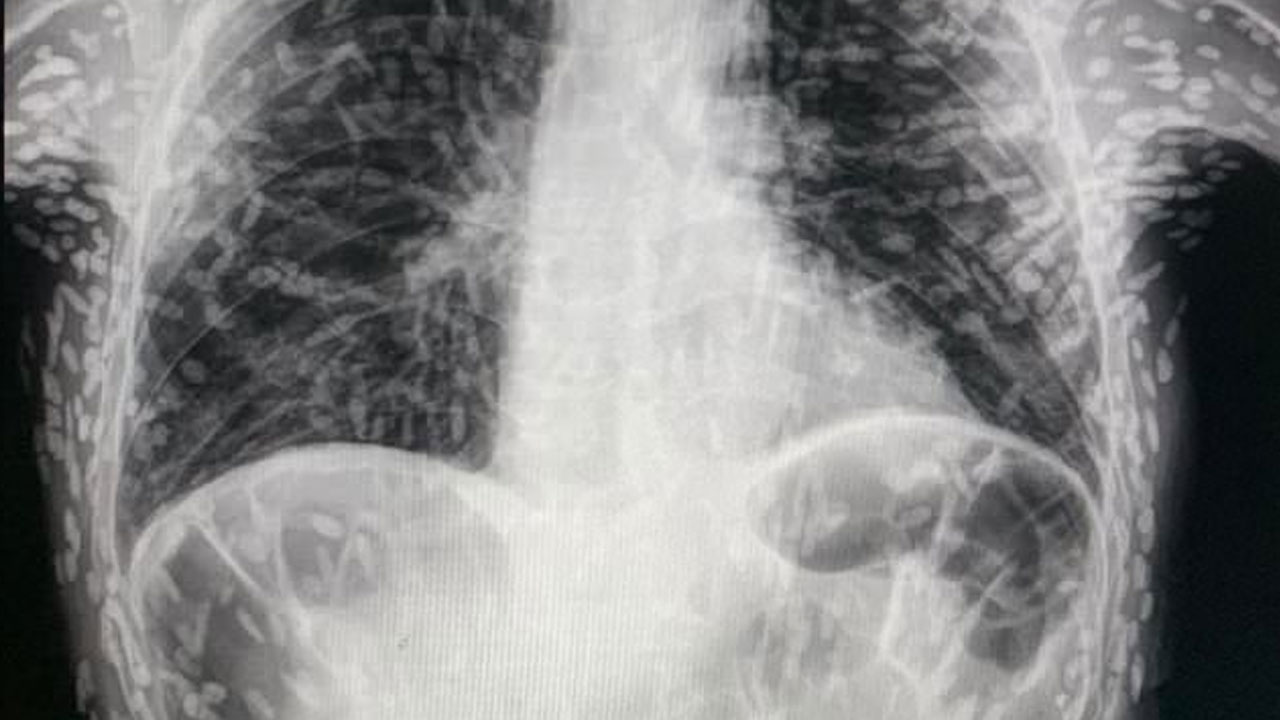

தொடர் இருமலுக்காக சிகிச்சை பெற வேண்டி மருத்துவமனையை அணுகியுள்ள ஒருவர் எடுத்த எக்ஸ்-ரே ஸ்கேனின் புகைப்படம் ஒன்று இணையத்தில் வைரலாகிவருகிறது. பார்த்தாலே திகிலில் உறைந்துதுபோகவைக்கும் அளவிற்கு அந்தப் புகைப்படம் அருவருப்பையும், அதே சமயம் அதிர்ச்சியையும் தருகிறது.

பிரேசில் நாட்டைச் சேர்ந்த அந்த நபரின் உடலுக்குள் வெள்ளை நிறத்தில் ஏதோ புள்ளிகள் போன்ற உருவம் படர்ந்திருப்பது புகைப்படத்தில் தெரிகிறது. அது வேறொன்றுமில்லை. பாரசைட் என்று சொல்லப்படும் ஒருவகை ஒட்டுண்ணிப் புழு தான். இந்த நிலைக்கு சிஸ்டிசெர்கோசிஸ் என்று பெயரிடப்பட்டுள்ளது.

இவ்வாறான லார்வாப் புழுக்கள் பரவலின்போது தலைவலி, வலிப்பு, குழப்ப மனநிலை, தலைச்சுற்றல் மற்றும் மூளையில் அதிக நீரை உருவாக்கும் ஹைட்ரோசெபாலஸ் போன்ற பிரச்சினைகளை உண்டாக்கும் என்று இப்புகைப்படங்களை வெளியிட்ட மருத்துவர் விட்டர் போரின் தெரிவிக்கிறார். மேலும் இவை கண்களை அடையும்போது பார்வையை மங்கலாக்கவும் செய்யலாம் என்று அவர் தெரிவிக்கிறார்.

உலகின் சில பகுதிகளில் ஏற்படும் கால்-கை வலிப்பு நிகழ்வுகளில் 70% பாதிப்புகளுக்கு மூளையில் வளரும் டேனியா சோலியம் என்ற லார்வா நீர்க்கட்டிகளே காரணமாக இருப்பதாக உலக சுகாதார நிறுவனம் தெரிவிக்கிறது. ஆண்டுக்கு சுமார் 2.5 மில்லியன் மக்கள் டேனியா சோலியம் நோயால் பாதிக்கப்படுவதாகக் கருதப்படுகிறது. இது பொதுவாக ஆசியா, தென் அமெரிக்கா மற்றும் கிழக்கு ஐரோப்பாவின் ஏழ்மையான மக்கள் வாழும் பகுதிகளில் கண்டறியப்படுகிறது.